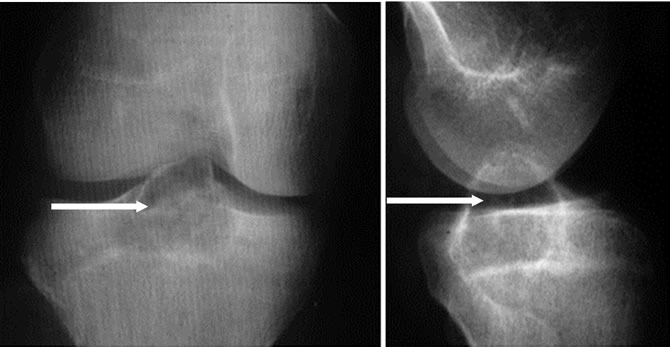

Aspect radiologique typique

Lacune épiphyso métaphysaire lytique pure

Ovalaire ou arrondie

Discrète soufflure de l'os

Parfois trabéculée

Limitée par un fin liseré condensé

Tumeurs à cellules géantes calmes

Limites nettes, condensées, Cloisons.

Tumeur agressive : rupture corticale et envahissement des parties molles

Tumeur à cellules géantes agressive révélée par une fracture déplacée chez une femme de 48 ans

La tumeur à cellules géantes bénigne peut envahir les parties molles